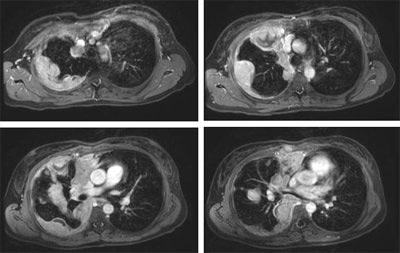

Four 3D Gradient echo images on a middle aged man who presented with circumferential pleural metastases from an invasive thymoma.